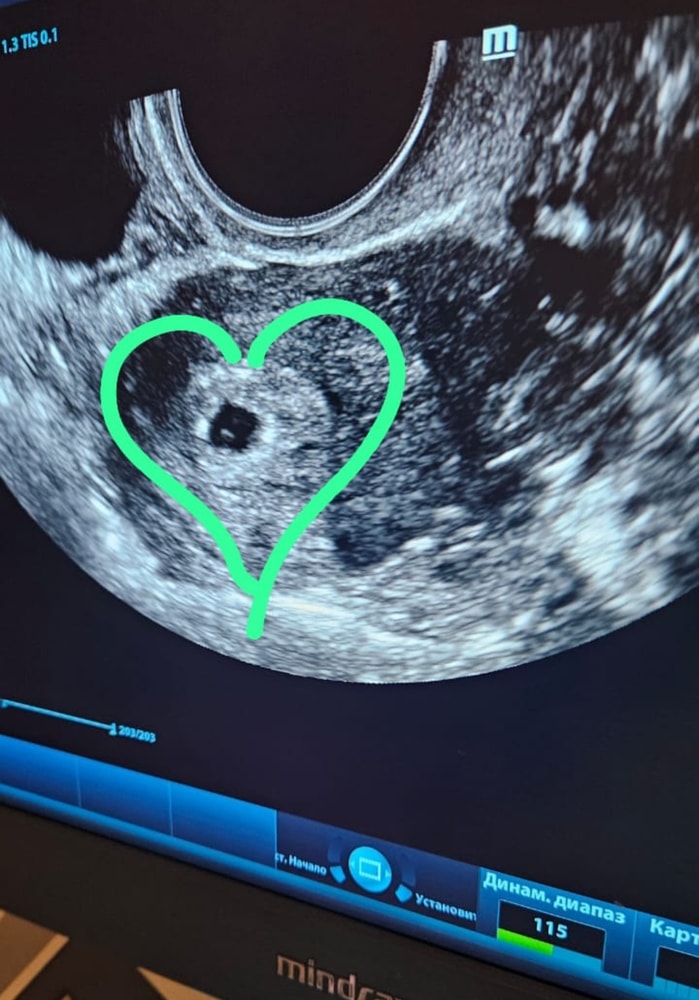

Результаты УЗИЗагремела в больницу! Вчера на 17 дпп полилась кровь, сгустки😱 в голове много мыслей...Среагировала сразу, знала, что у экошниц часто кровит на ранних сроках. Вызвала скорую, поставила укол прог масло, свечу папаверин, выпила транексам и легла ждать... Приехали быстро. Но вот оформление долго шло в клинике, вся разнервничалась... В палате легче стало..Легла, поставили капельницу, уколы. Сегодня узи, плодное яйцо на месте + жм.🙏❤️💙 Соответвует сроку!! Отслойка, стала меньше. Будем лежать, наблюдать, сохраняться. Девочки, берегите себя и в аптечке своей все подручные медикаменты!